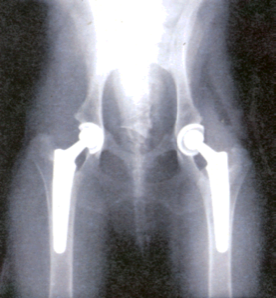

Los tratamientos conservadores que un traumatologo ortopedista realiza pueden ser las reducciones incruentas, vendajes blandos, la colocación de férulas y yesos asi como tracciones blandas ó esqueléticas. Los tratamientos quirúrgicos implican una acción sobre situaciones de mayor gravedad o que requieran cirugía como único medio de solución. Para ello se emplean: la reducción abierta, agujas de Kirschner y Steinmann, placas y tornillos de osteosíntesis, dispositivos clavo-placa y tornillo-placa, clavos intramedulares (Küntscher, Gross-Kempf, Ender, Russ), fijadores externos (Hoffman, Ilizarov, monolaterales), injertos óseos, cementos óseos y prótesis para reemplazos articulares.